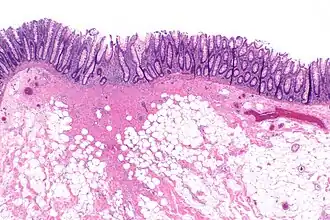

![]() Micrograph showing a colorectal polypectomy scar. H&E stain. | |